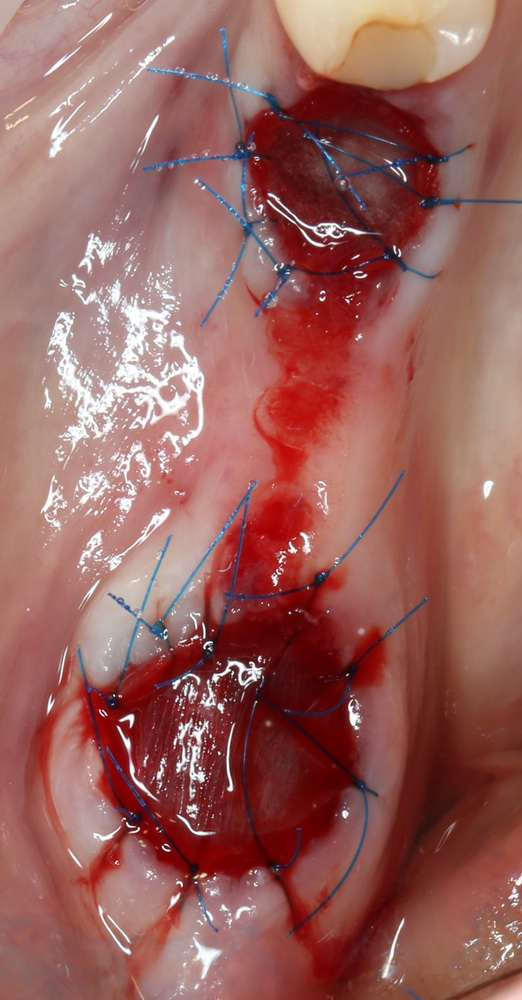

Далее — обычные рекомендации после удаления зубов, контрольный осмотр через день:

и через неделю:

Пациенту даются обычные рекомендации после удаления зуба. Контрольный осмотр — через день:

И вот тут я подумал, что пришла беда. Решил, что Mucograft Seal развалился (пациент курит), что с дня на день нужно ждать альвеолит.

Но оказалось иначе. Никаких беспокойств, никаких проблем, никакого дискомфорта. Сняли швы через неделю, с пациентом расстались на полтора месяца.